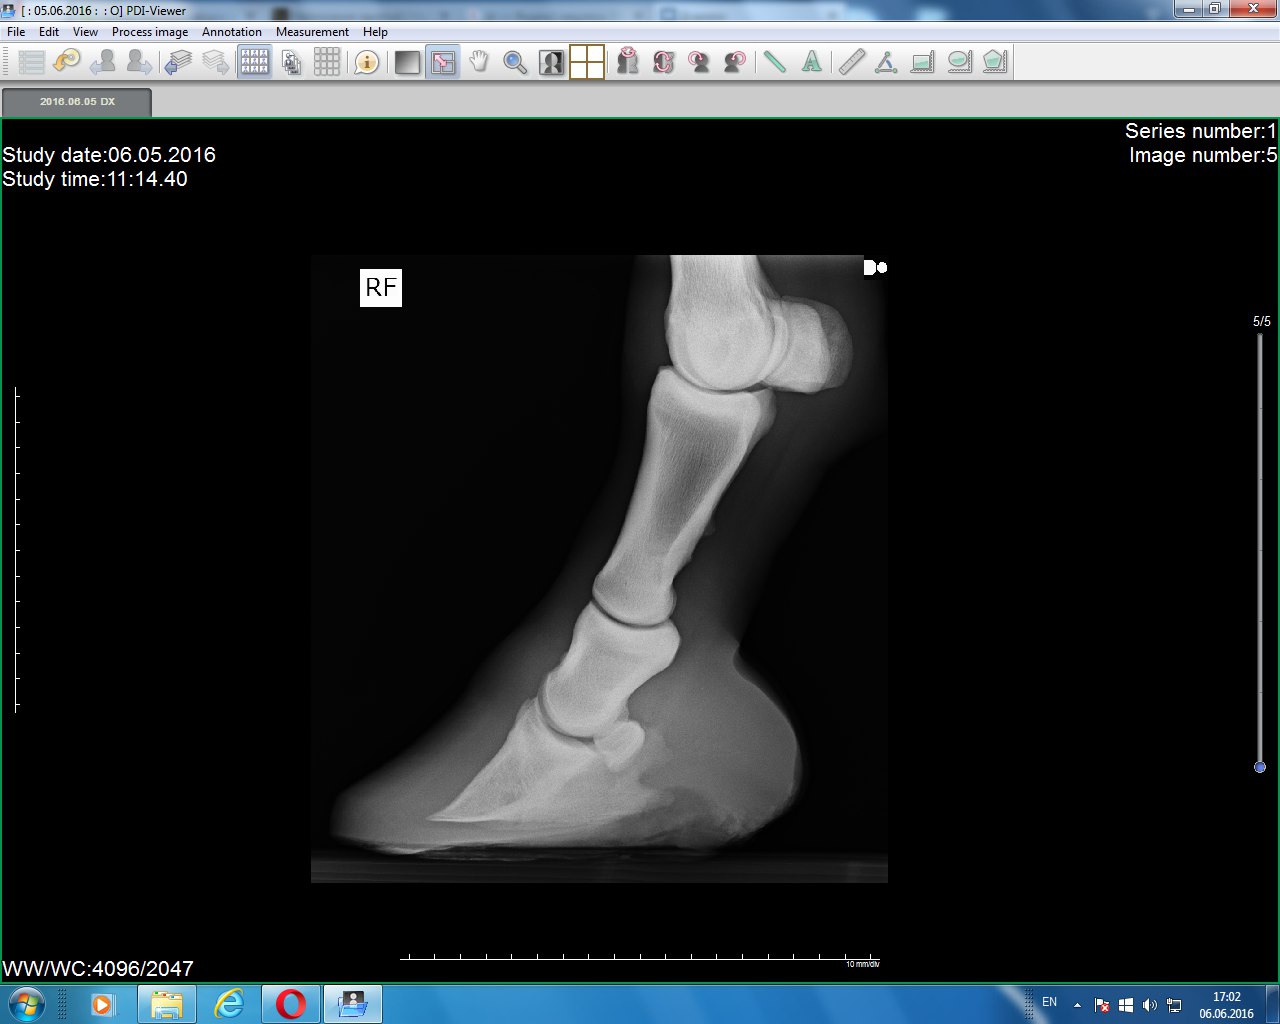

Правый перед(2016) Тут лошадь чуть согнула ногу, потому постав такой странный)

Левый и правый перед (2016)